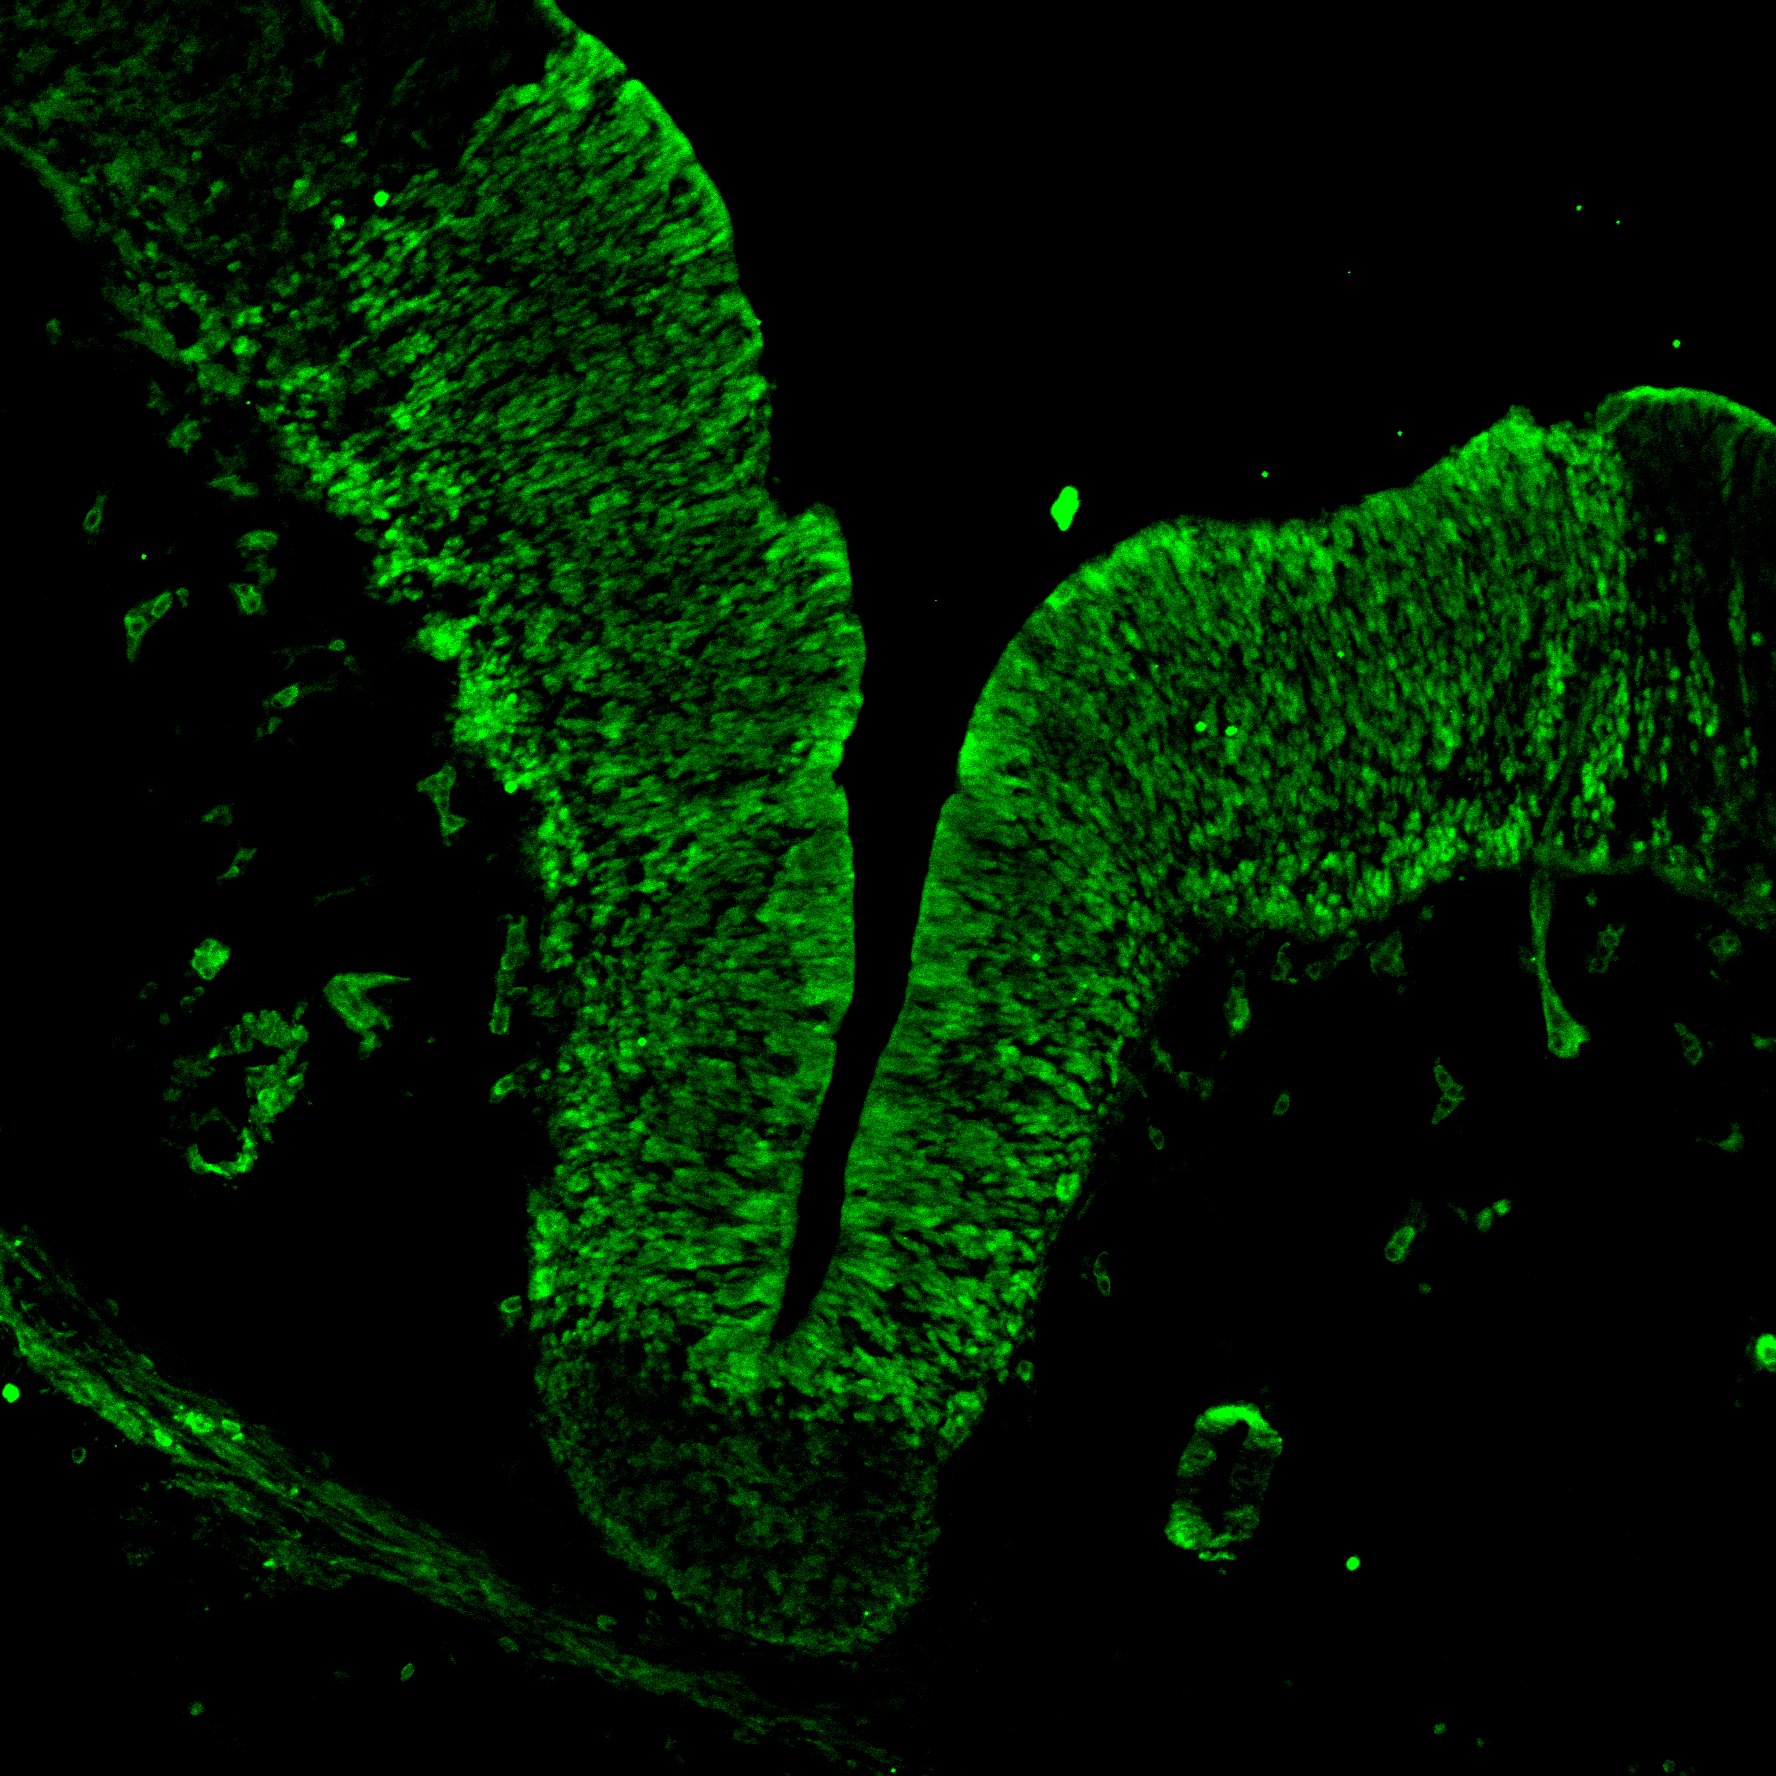

An anatomical analysis of the developing human midbrain from 6 post-conceptional weeks (PCW) to 22 PCW reveals increased tissue complexity, characterized by the emergence of dopaminergic nuclei, as highlighted by immunofluorescence analysis for tyrosine hydroxylase (TH).

MAP2

11PCW human midbrain

SOX2